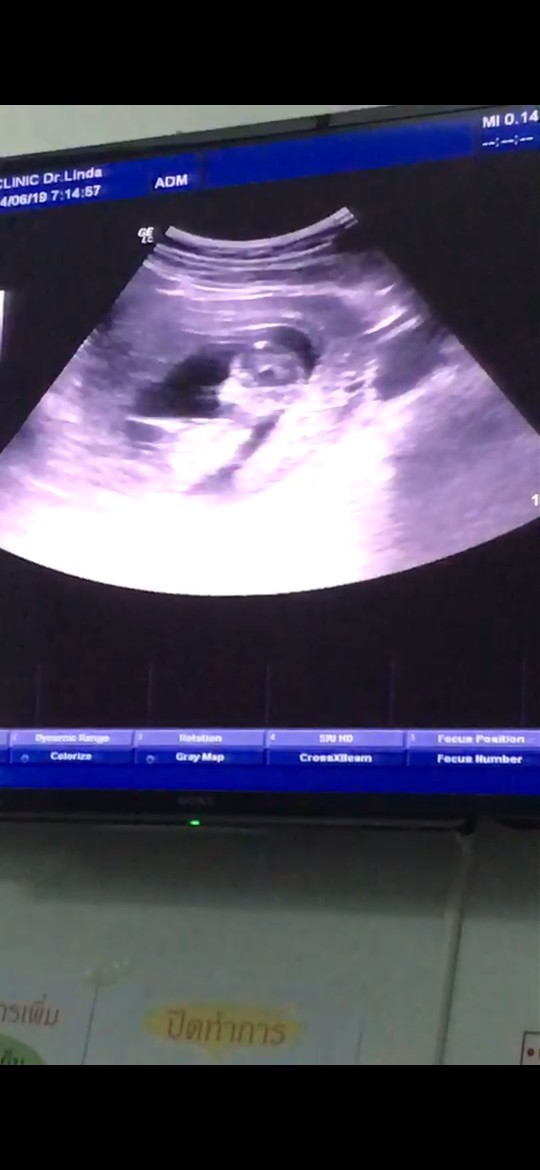

มาอวดภาพแรกของเจ้าตัวน้อยกันคะ

อยากเห็นภาพแรกของเจ้าตัวน้อย. ของแม่ๆ. แต่ละบ้านบ้างอะคะ. มาแชร์ประสบการณ์กันได้นะคะ❤️

ตอน10 W 5 D ค่ะ